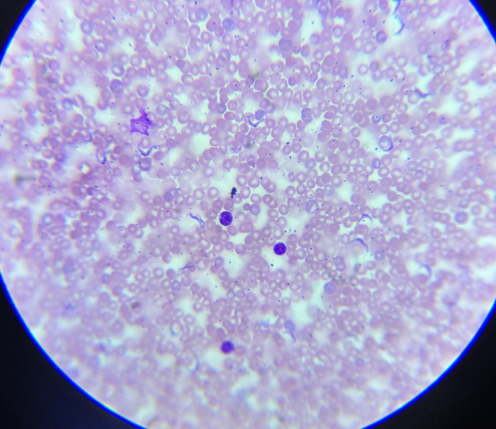

plasmodium falciparum stadia schizogonii krwinkowej

plasmodium falciparum stadia schizogonii krwinkowej